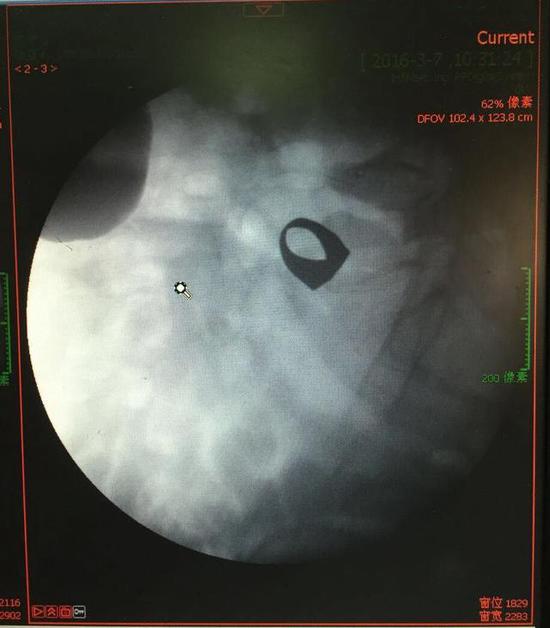

考慮到患者年齡較大,有冠心病,曾經(jīng)中過(guò)風(fēng),高血壓極高危級(jí),遂把老人安排在帶有監(jiān)護(hù)的病房,立即給予吸氧,補(bǔ)液等治療。醫(yī)院立刻開啟綠色通道,醫(yī)護(hù)人員專門陪伴病人做了增強(qiáng)CT,腹部平片,和碘水造影,確定戒指的位置。檢查結(jié)果提示戒指位于右下腹小腸內(nèi),距回盲瓣體表投影約5cm。

此時(shí)一個(gè)又一個(gè)大大的疑問(wèn)出現(xiàn)在每個(gè)在場(chǎng)的醫(yī)護(hù)人員腦海中,戒指還在小腸里嗎?戒指在哪個(gè)位置呢?夏教授立刻聯(lián)系放射科,拍片子,發(fā)現(xiàn)戒指已經(jīng)移動(dòng)了,從右側(cè)移動(dòng)到了左側(cè)去了。放射科醫(yī)師建議,戒指有可能會(huì)繼續(xù)沿腸道下行,如果過(guò)了回盲瓣,就可以自行排出,免除手術(shù)痛苦。教授們采納了這個(gè)意見(jiàn),立即給予促進(jìn)胃腸道動(dòng)力藥,枸櫞酸莫沙必利片,每日口服三次,另外配合灌腸治療,促進(jìn)腸道蠕動(dòng),利于戒指排出。